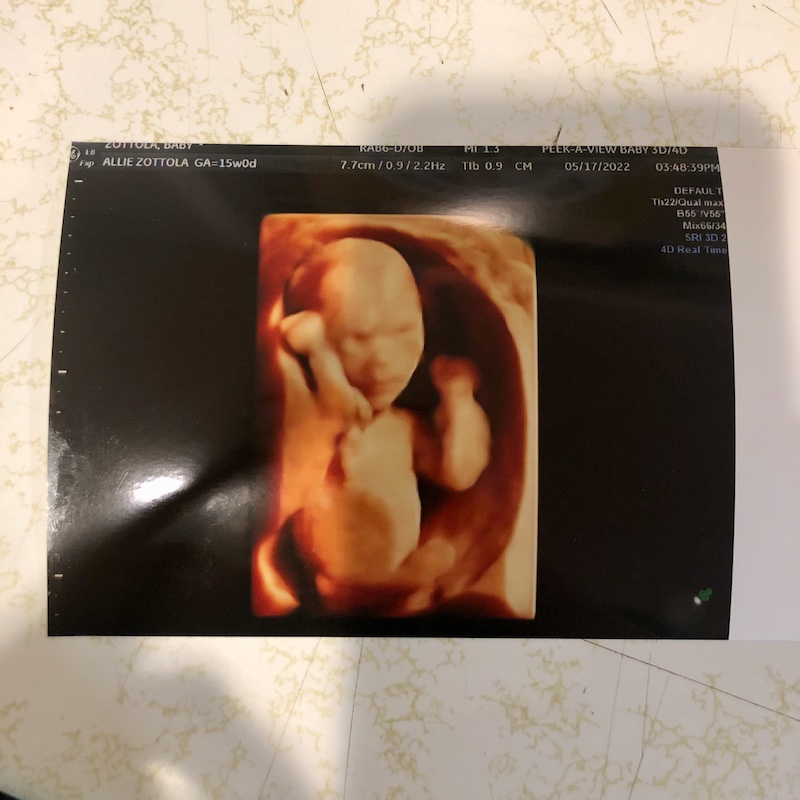

Finding out was great! I had a 15 week ultrasound and it was actually perfect timing because I had food poisoning a few days before that and was fearful the incidence had hurt the baby somehow.

But alas, I went to that ultrasound and right away I saw baby boy and his heartbeat and all was well. God is GOOD! What a relief ❤️ I don’t know if other pregnant women are in the same boat as me, but I’d have an ultrasound every day just to see him and make sure everything is okay. Am I crazy? Maybe 😉